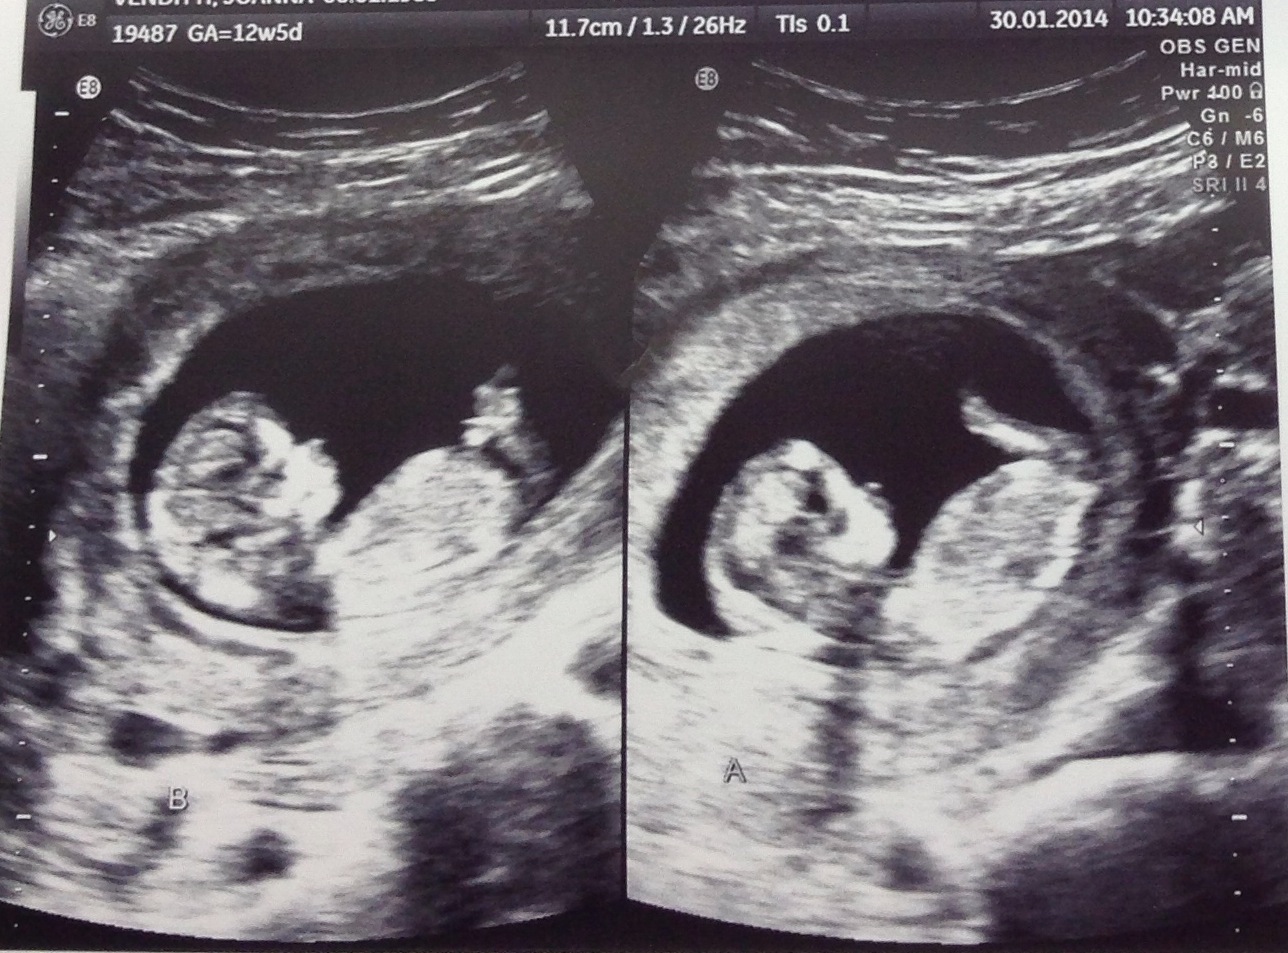

Can An Ultrasound Detect Twins At 12 Weeks at Martha Meredith blog How Can A Twin Hide On Ultrasound The fetuses are forced to stay together in one. The positioning of the twins in the womb can sometimes result in one twin being fully or partially obscured by the other, making it. How early can you see twins on an ultrasound? Most patients have their first. The earliest you can typically expect to see twin fetuses on an ultrasound. How Can A Twin Hide On Ultrasound.